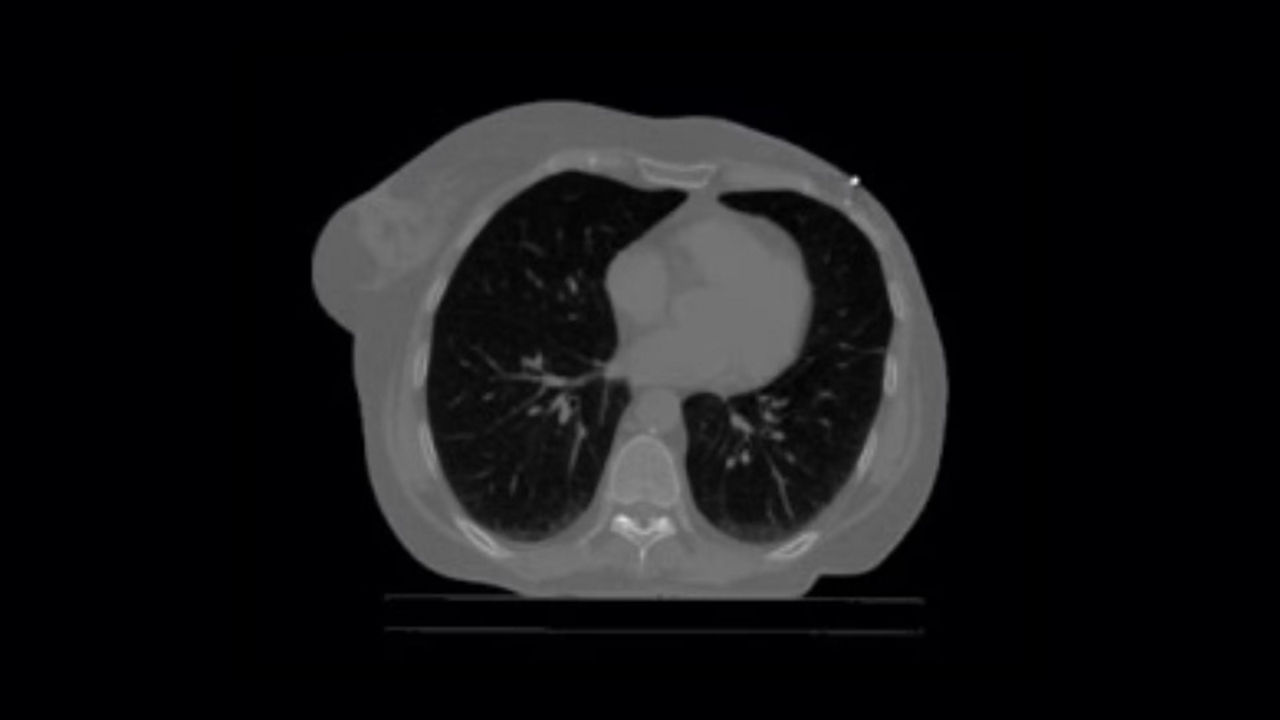

<p>Thoracic VCAR with GSI Pulmonary Perfusion</p>

Learn more